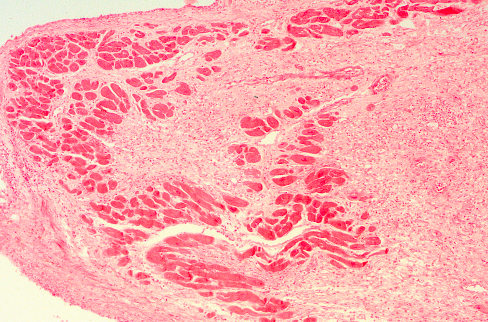

7

Q

What do you see?

A

- This is an intermediate myocardial infarction of 1 to 2 weeks in age

- Note that there are remaining normal myocardial fibers at the top

- Below these fibers are many macrophages along with numerous capillaries and little collagenization